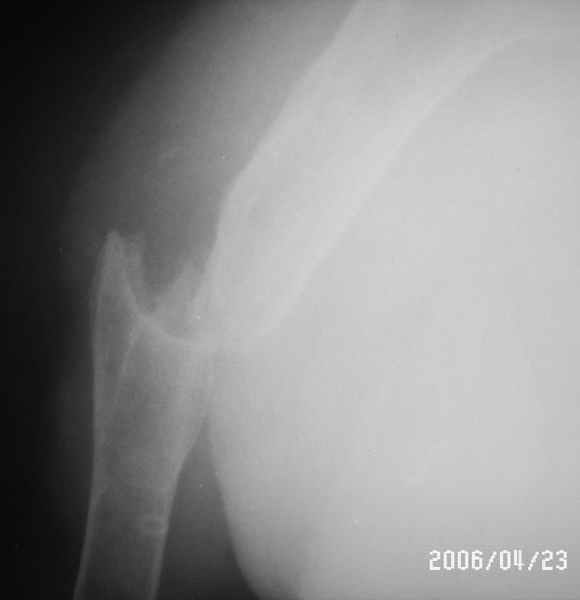

Уважаемые коллеги! Помогите в выборе тактики лечения больной Р.,56 лет, с болтающимся ложным суставом с/3 правой плечевой кости 2-х летней давности. В анамнезе - бронхиальная астма, гормонозависимая форма, ожирение III cт.

Травма - автодорожная, получила закрытый многооскольчатый перелом диафиза плечевой кости со смещением (от метафиза до метафиза), в экстренном порядке нами произведен закрытый остеосинтез стержневым аппаратом, отломки удалось сопоставить анатомически. В дальнейшем больная выпала из поля зрения. Как потом выяснилось, после снятия стержневого аппарата, больная долечивалась по Илизарову специалистом из г. Кургана. Аппарат Илизарова удален из-за нагноения мягких тканей. Последние два года работая бухгалтером, фиксирует плечо ортезом. Теперь вновь обратилась к нам для ликвидации ложного сустава.